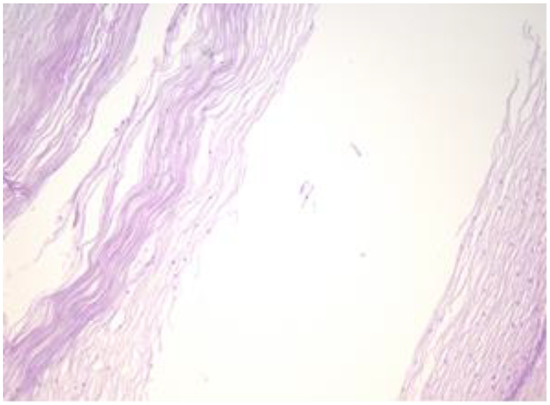

The exo-cervix shows a cystic structure in the deeper layers that is filled with an amorphic, eosinophilic, lamellar substance (Figure 3). The cyst is lined by stratified epithelium resembling squamous epithelium that reminds us of the typical structure found at the level of the endo-exocervical junction (Figure 4).

Figure 3. Exo-cervix shows a cystic structure in the deeper layers that is filled with an amorphic, eosinophilic, lamellar substance (HE staining, 5×).

Figure 4. Cyst is lined by a stratified epithelium that resembles a squamous epithelium, similar in appearance to the endo-exocervical junctional area (HE staining, 10×).